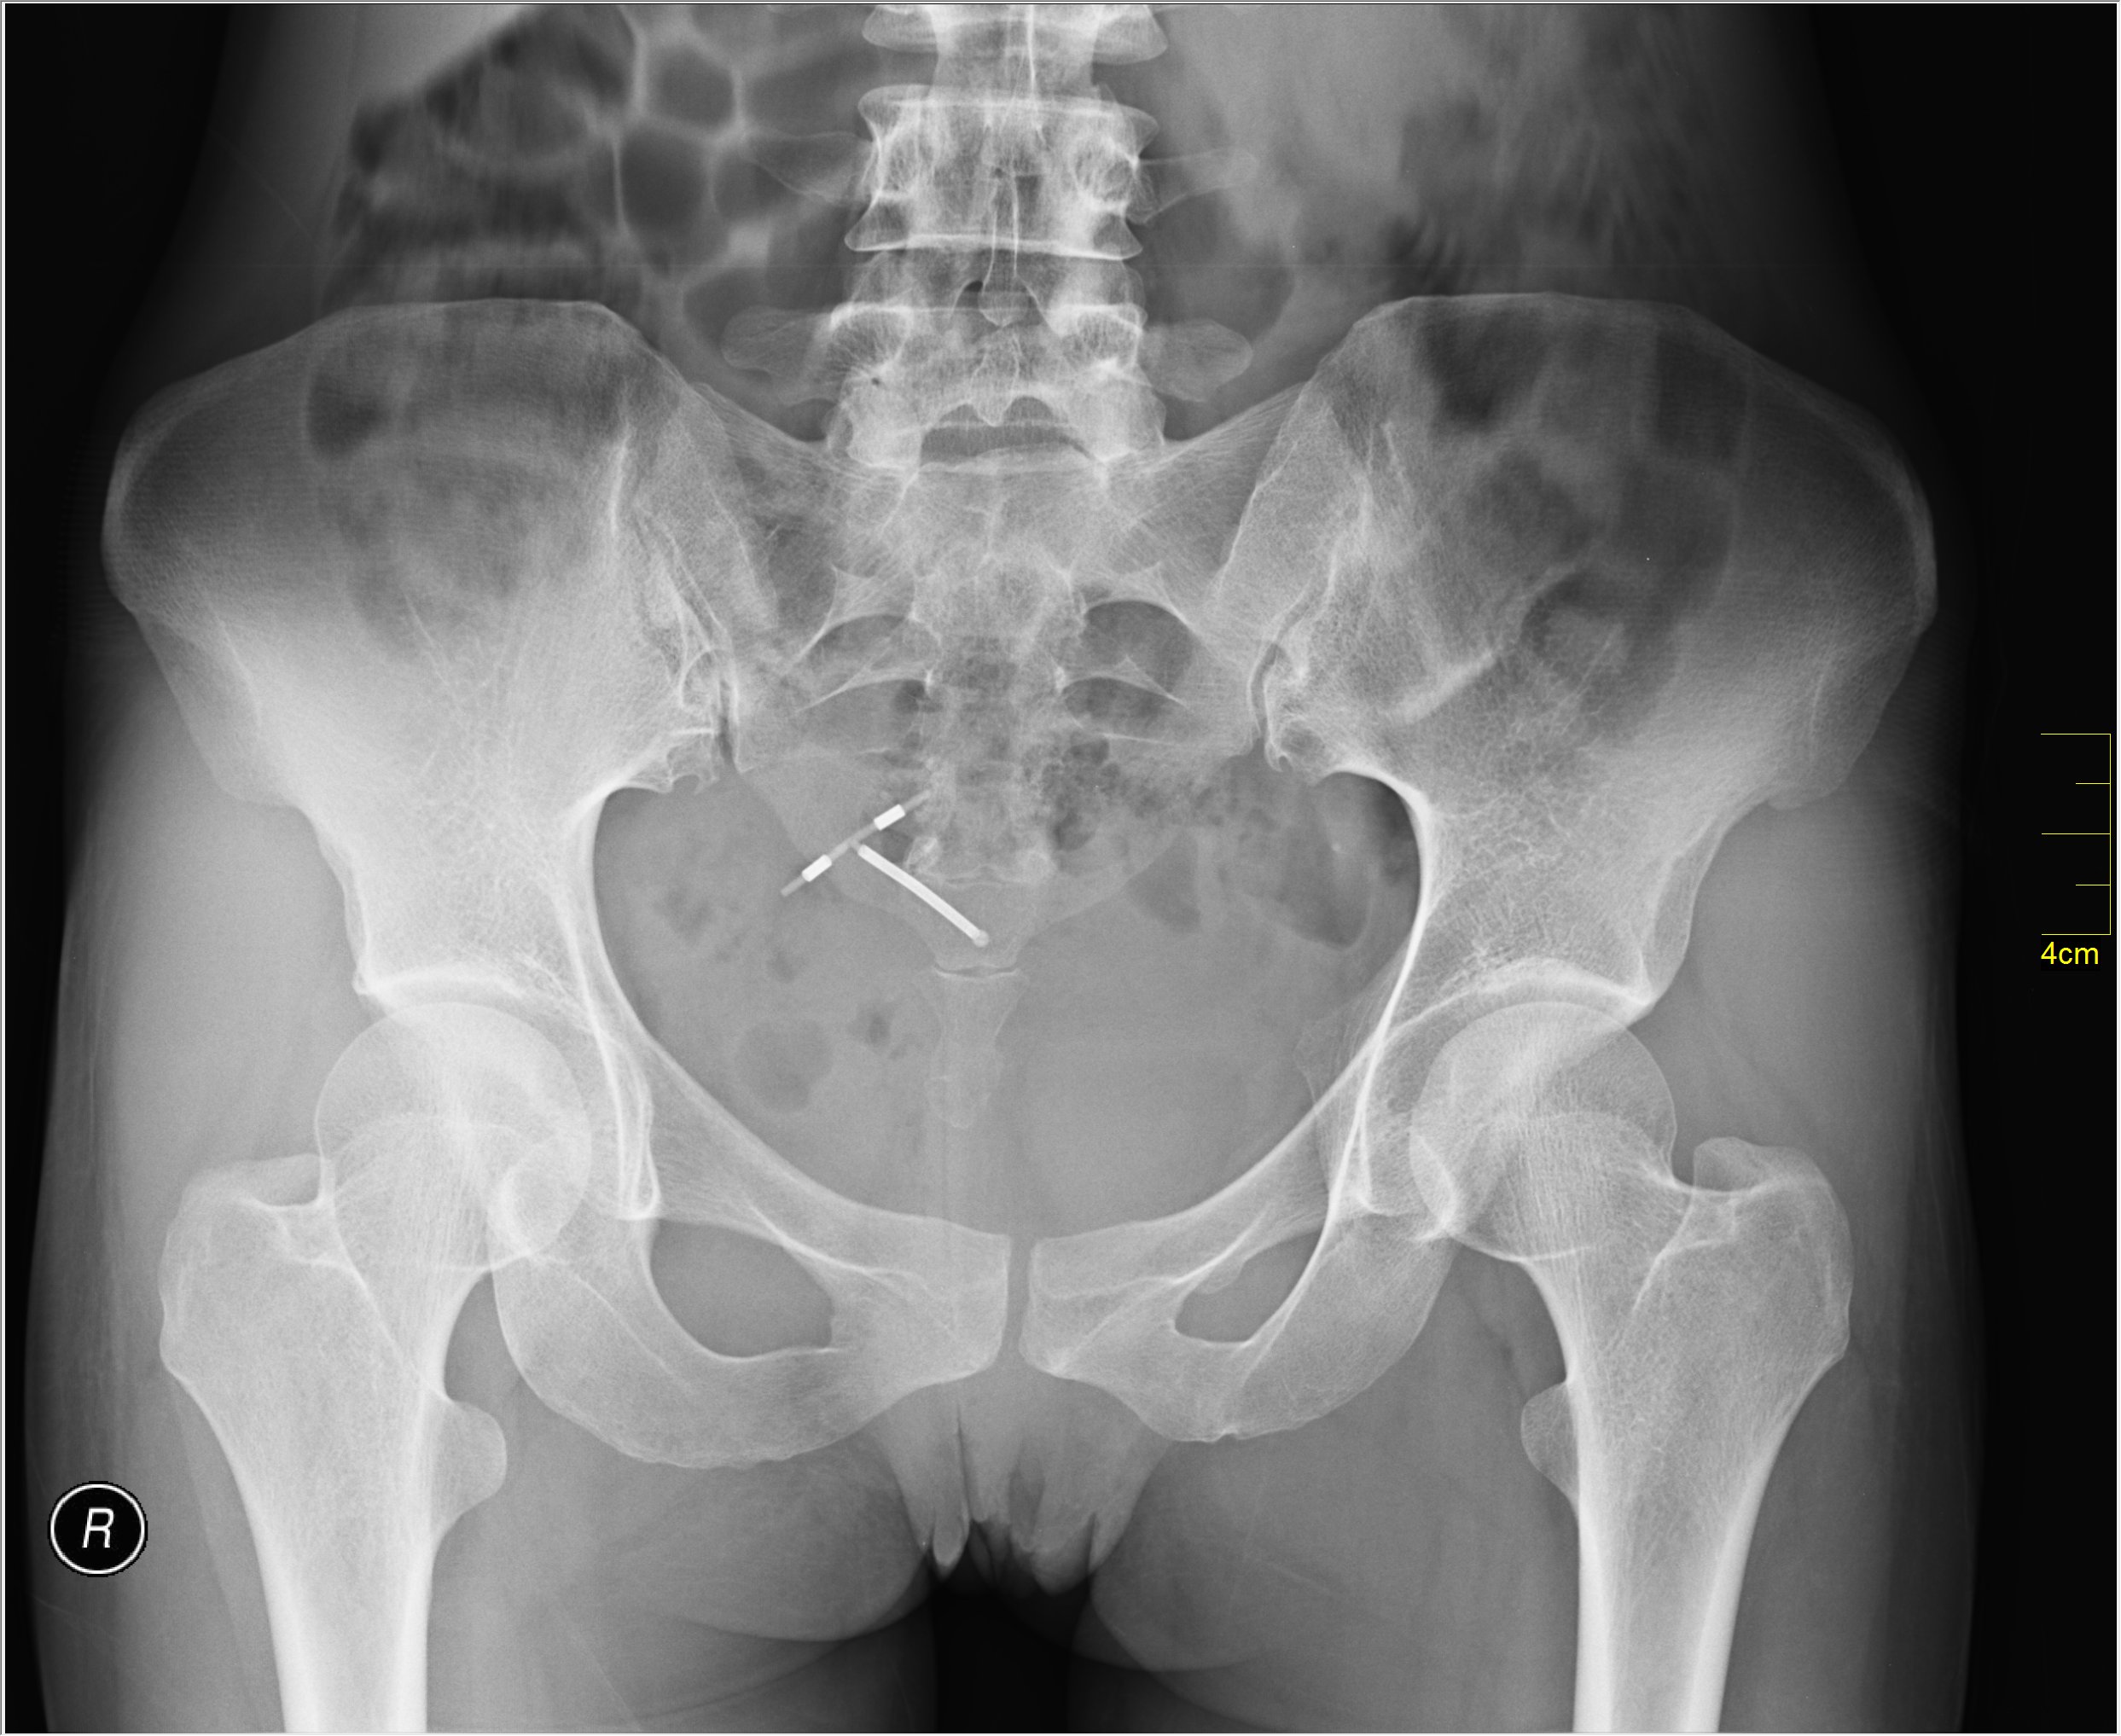

5. 삽입 및 제거

IUD 삽입 및 제거는 의료 전문가(한국에서는 산부인과 의사)가 시행한다.[95] 삽입 시 통증 완화를 위해 국소 리도카인을 사용할 수 있다.[170] 삽입 절차는 보통 5-10분 정도 소요되며,[172] 질경을 사용하여 자궁경부를 확인하고, 삽입기를 통해 IUD를 자궁 내에 위치시킨다.[171]

산후 즉시 삽입도 가능하다.[173] 자궁에서 태반을 제거한 후 IUD를 삽입하며, 질 분만 후에는 태반 겸자나 손을 사용하고, 제왕 절개술 후에는 겸자나 손으로 IUD를 자궁에 삽입한다.[173][174][175]